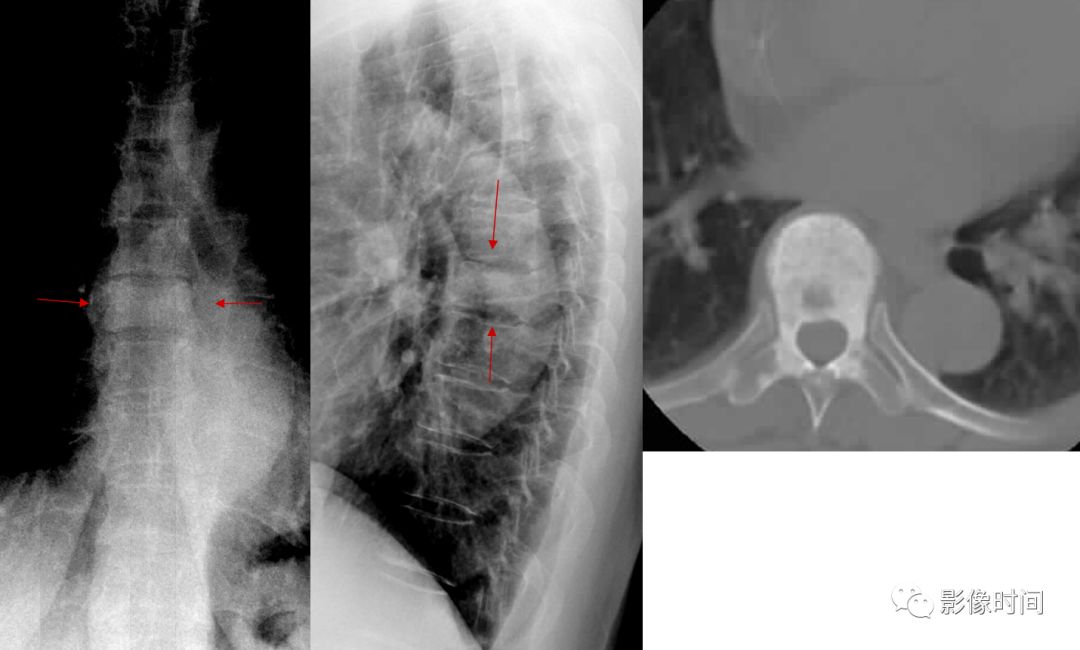

10栅栏征

栅栏征(The Palisade sign),也称灯芯绒椎体(corduroy vertebra)或灯芯绒征(corduroy sign)

脊椎椎体因病变导致骨小梁吸收、稀疏,为满足承重需要,存留的纵向骨小梁粗大;粗大骨小梁间以细条状密度减低区,形成栅栏样影像,故称栅栏征或灯芯绒椎体。

栅栏征最常见于血管瘤,以单个脊椎居多;骨质疏松如泛发性骨质增生症、老年性骨质疏松等亦可呈现此类表现,一般见于下胸椎、上部腰椎的多个椎体,只是伴有普遍的骨密度减低。有时自颈椎至腰椎全部椎体均出现栅栏征。栅栏征主要见于椎体。

典型病例

病例 1,脊柱血管瘤。胸腰椎 CT 冠状位、矢状位 MPR 重建示胸 12 椎体松质骨密度降低,其中可见粗大骨小梁呈栅栏状。

病例 2,67 岁女性,椎体血管瘤。腰椎侧位片示胸 12 及腰 3 椎体呈现栅栏征,磁共振检查证实为血管瘤。

病例 3,泛发性骨质增生症,男,47 岁。A-C.颈椎、胸椎、腰椎侧位片,显示所有椎体纵向骨小梁粗大、稀疏;粗大骨小梁间以细条状密度减低区,呈栅栏征。D-G.胸、腰椎 MR 冠状、矢状位图像,粗大、稀疏的示纵向骨小梁呈低信号,在邻近富脂肪骨髓信号衬托下呈典型的栅栏征

(引自丁香园,华夏览雄 http://radiology.dxy.cn/bbs/topic/34521015)参考文献:陈凡. 骨关节 X 线征. 武汉:湖北人民出版社,1987:94-95.